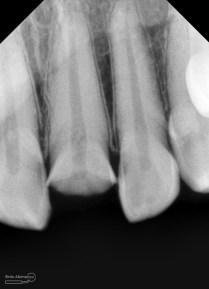

dan ini foto ronsen nya…

Foto radiografis gigi 11 21 22 yang mengalami fraktur

Dari pemeriksaan radiografis lokasi fraktur menyerempet kamar pulpa pada ketiga gigi tersebut… Saya sampaikan kepada pasien bahwa ketiga gigi tersebut memerlukan perawatan saluran akar terlebih dahulu baru kemudian dilanjutkan dengan restorasi indirek… kenapa saya pilih restorasi indirek? Pertimbangannya adalah sisa struktur mahkota gigi yang ada bila hanya di “sambung” dengan restorasi direk dalam jangka panjang rentan mengalami kerusakan, yang kedua pemilihan warna akan lebih maksimal pada kasus ini…. Pasien setuju dengan rencan perawatan yang saya jelaskan…